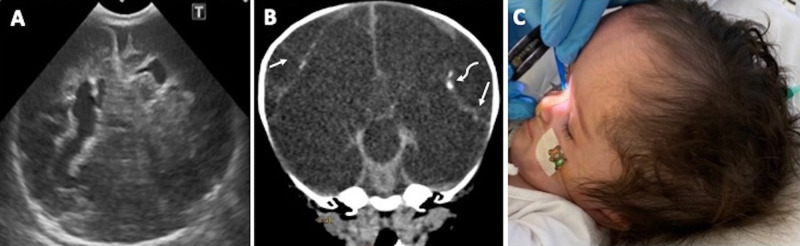

Hemorrhagic Destruction of the Brain, Subependymal Calcification, and Congenital Cataracts (HDBSCC) is a rare syndrome caused by biallelic mutations in the JAM3 gene with significant intrafamilial variability in clinical presentation and brain imaging phenotypes. The clinical presentation of HDBSCC includes severe recurrent hemorrhages involving the brain parenchyma and the ventricles beginning in utero and continuing in infancy together with dense central cataracts present at birth. This comprehensive review documents reported cases on this unique condition and describes its genetic, neuroradiologic and ophthalmic features. It should be included in the differential diagnosis of children with congenital cataracts and neurodevelopmental abnormalities. Unique clinical, imaging findings and genetic testing can help the diagnosis.

Abstract Image